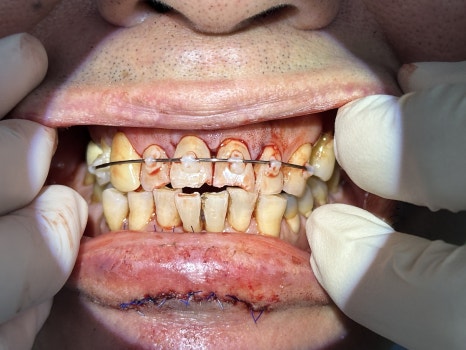

🖼️ Lip trauma photo / Front tooth fracture and fixation photo / X-ray photo

Lip laceration immediately after the trauma / Initial emergency treatment photo showing fixation of the dislocated front tooth

🔧 Root canal treatment and lip suturing, mid-treatment progress

The front tooth nerve had already become necrotic,

and we continued treatment in the direction of preserving the tooth by immediately performing root canal treatment to remove the infection.

The lip was carefully sutured to minimize scarring,

and afterward it healed naturally, with no major inconvenience in daily life.